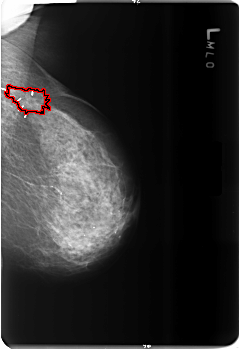

B_3513_1.LEFT_MLO

FILE: B_3513_1.LEFT_MLO.OVERLAY

TOTAL_ABNORMALITIES 1

ABNORMALITY 1

LESION_TYPE MASS SHAPE ARCHITECTURAL_DISTORTION MARGINS ILL_DEFINED

ASSESSMENT 2

SUBTLETY 5

PATHOLOGY BENIGN_WITHOUT_CALLBACK

TOTAL_OUTLINES 1

BOUNDARY